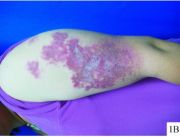

| 2021年7月26日 (一) 20:01 | 皮肤损害.jpg (文件) |  |

22 KB | 77921020 | Uploaded with SimpleBatchUpload | 3 |

| 2021年7月26日 (一) 20:01 | 皮肤过敏.jpg (文件) |  |

20 KB | 77921020 | Uploaded with SimpleBatchUpload | 3 |